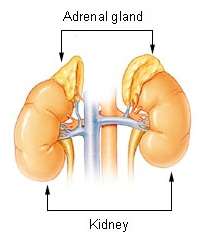

Adrenal gland

The adrenal gland is a major organ of the endocrine system that is located directly on top of the kidneys and is chiefly responsible for the synthesis of stress hormones that are released into the blood stream during a stress response. Cortisol is the major stress hormone released by the adrenal gland.

In addition to the locus coeruleus existing as a source of the neurotransmitter norepinephrine within the central nervous system, the adrenal gland can also release norepinephrine during a stress response into the body's blood stream, at which point norepinephrine acts as a hormone in the endocrine system.